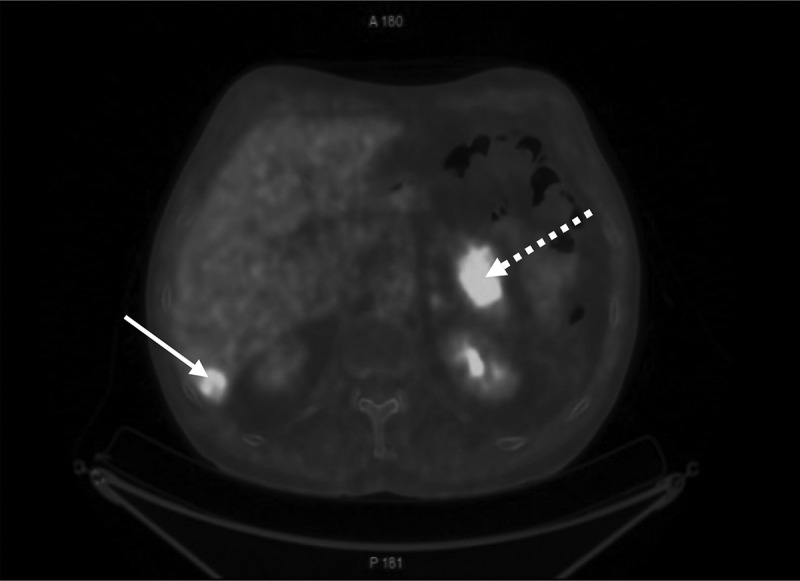

胰腺内镜超声引导细针穿刺活检(EUS-FNA)是许多内镜中心的常规检查项目,也是疑似胰腺癌诊断程序的一部分。由于经食道支气管镜超声引导细针穿刺活检术(EUS-B-FNA)能有效诊断纵隔和上腹部的病变,因此肺科医生对它的使用范围也大大扩展。下面的病例展示了 EUS-B-FNA 在一名患有非小细胞肺癌(NSCLC)和不明原因胰腺肿块的患者身上的安全性和可行性。一名曾被诊断为 NSCLC 的患者因怀疑 NSCLC 复发而被转诊至欧登塞大学医院呼吸内科。患者在同一手术中接受了支气管内超声引导(EBUS)-FNA检查,检查了多个疑似纵隔淋巴结,并对胰腺肿块进行了EUS-B-FNA联合检查。胰腺肿块和纵隔淋巴结的病理结果显示为鳞状细胞癌,由之前的 NSCLC 转移而来。我们在此证明,EUS-B-FNA 是一种可行且安全的技术,可用于从肺癌受检患者的胰腺病变中获取组织样本。

Endoscopic ultrasound-guided fine needle aspiration biopsy (EUS-FNA) of the pancreas is performed routinely in many endoscopic centers as part of the diagnostic set-up for suspected pancreatic cancer. The use of transesophageal bronchoscopic ultrasound-guided fine needle aspiration (EUS-B-FNA) by pulmonologists has expanded significantly, since it enables effective diagnosis of lesions in the mediastinum and upper abdomen. The following case demonstrates the safety and feasibility of EUS-B-FNA in a patient with non-small cell lung cancer (NSCLC) cancer and a pancreatic mass of unknown origin. A patient who was previously diagnosed with NSCLC was referred to the Department of Respiratory Medicine, Odense University Hospital due to suspected recurrence of NSCLC. The patient underwent endobronchial ultrasound guided (EBUS)-FNA from several suspected mediastinal lymph nodes and combined EUS-B-FNA from a pancreatic mass during the same procedure. Pathology results from the pancreatic mass and from the mediastinal lymph nodes showed squamous-cell carcinoma, metastasis from the previous NSCLC. We here by demonstrated that EUS-B-FNA is a feasible and safe technique to obtain tissue samples from pancreatic lesions in patients under investigation for lung cancer.